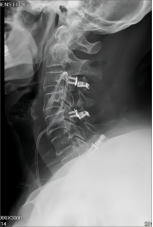

颈椎后路减压技术适用于:脊髓型颈椎病伴发育性或多节段退变性椎管狭窄者;多节段OPLL;颈椎黄韧带肥厚或骨化所致脊髓腹背受压者。有节段性不稳定者可以同时行侧块钛板螺钉或经椎弓根螺钉内固定、植骨融合术。我科在区域内率先开展颈椎单开门、双开门技术,颈椎椎板切除减压椎弓根内固定术,均获得满意疗效。